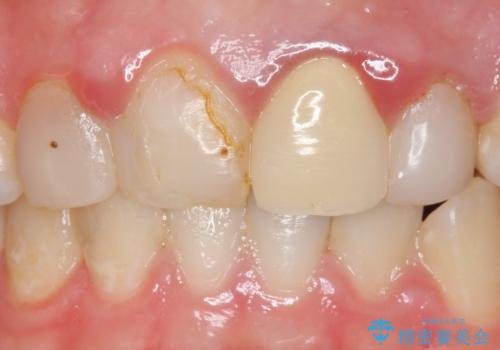

- 前歯の色・形を綺麗にしたいといらっしゃった方の症例です。

左上1、2の再根管治療終了後、オールセラミッククラウン(スペシャル)による補綴を行いました。